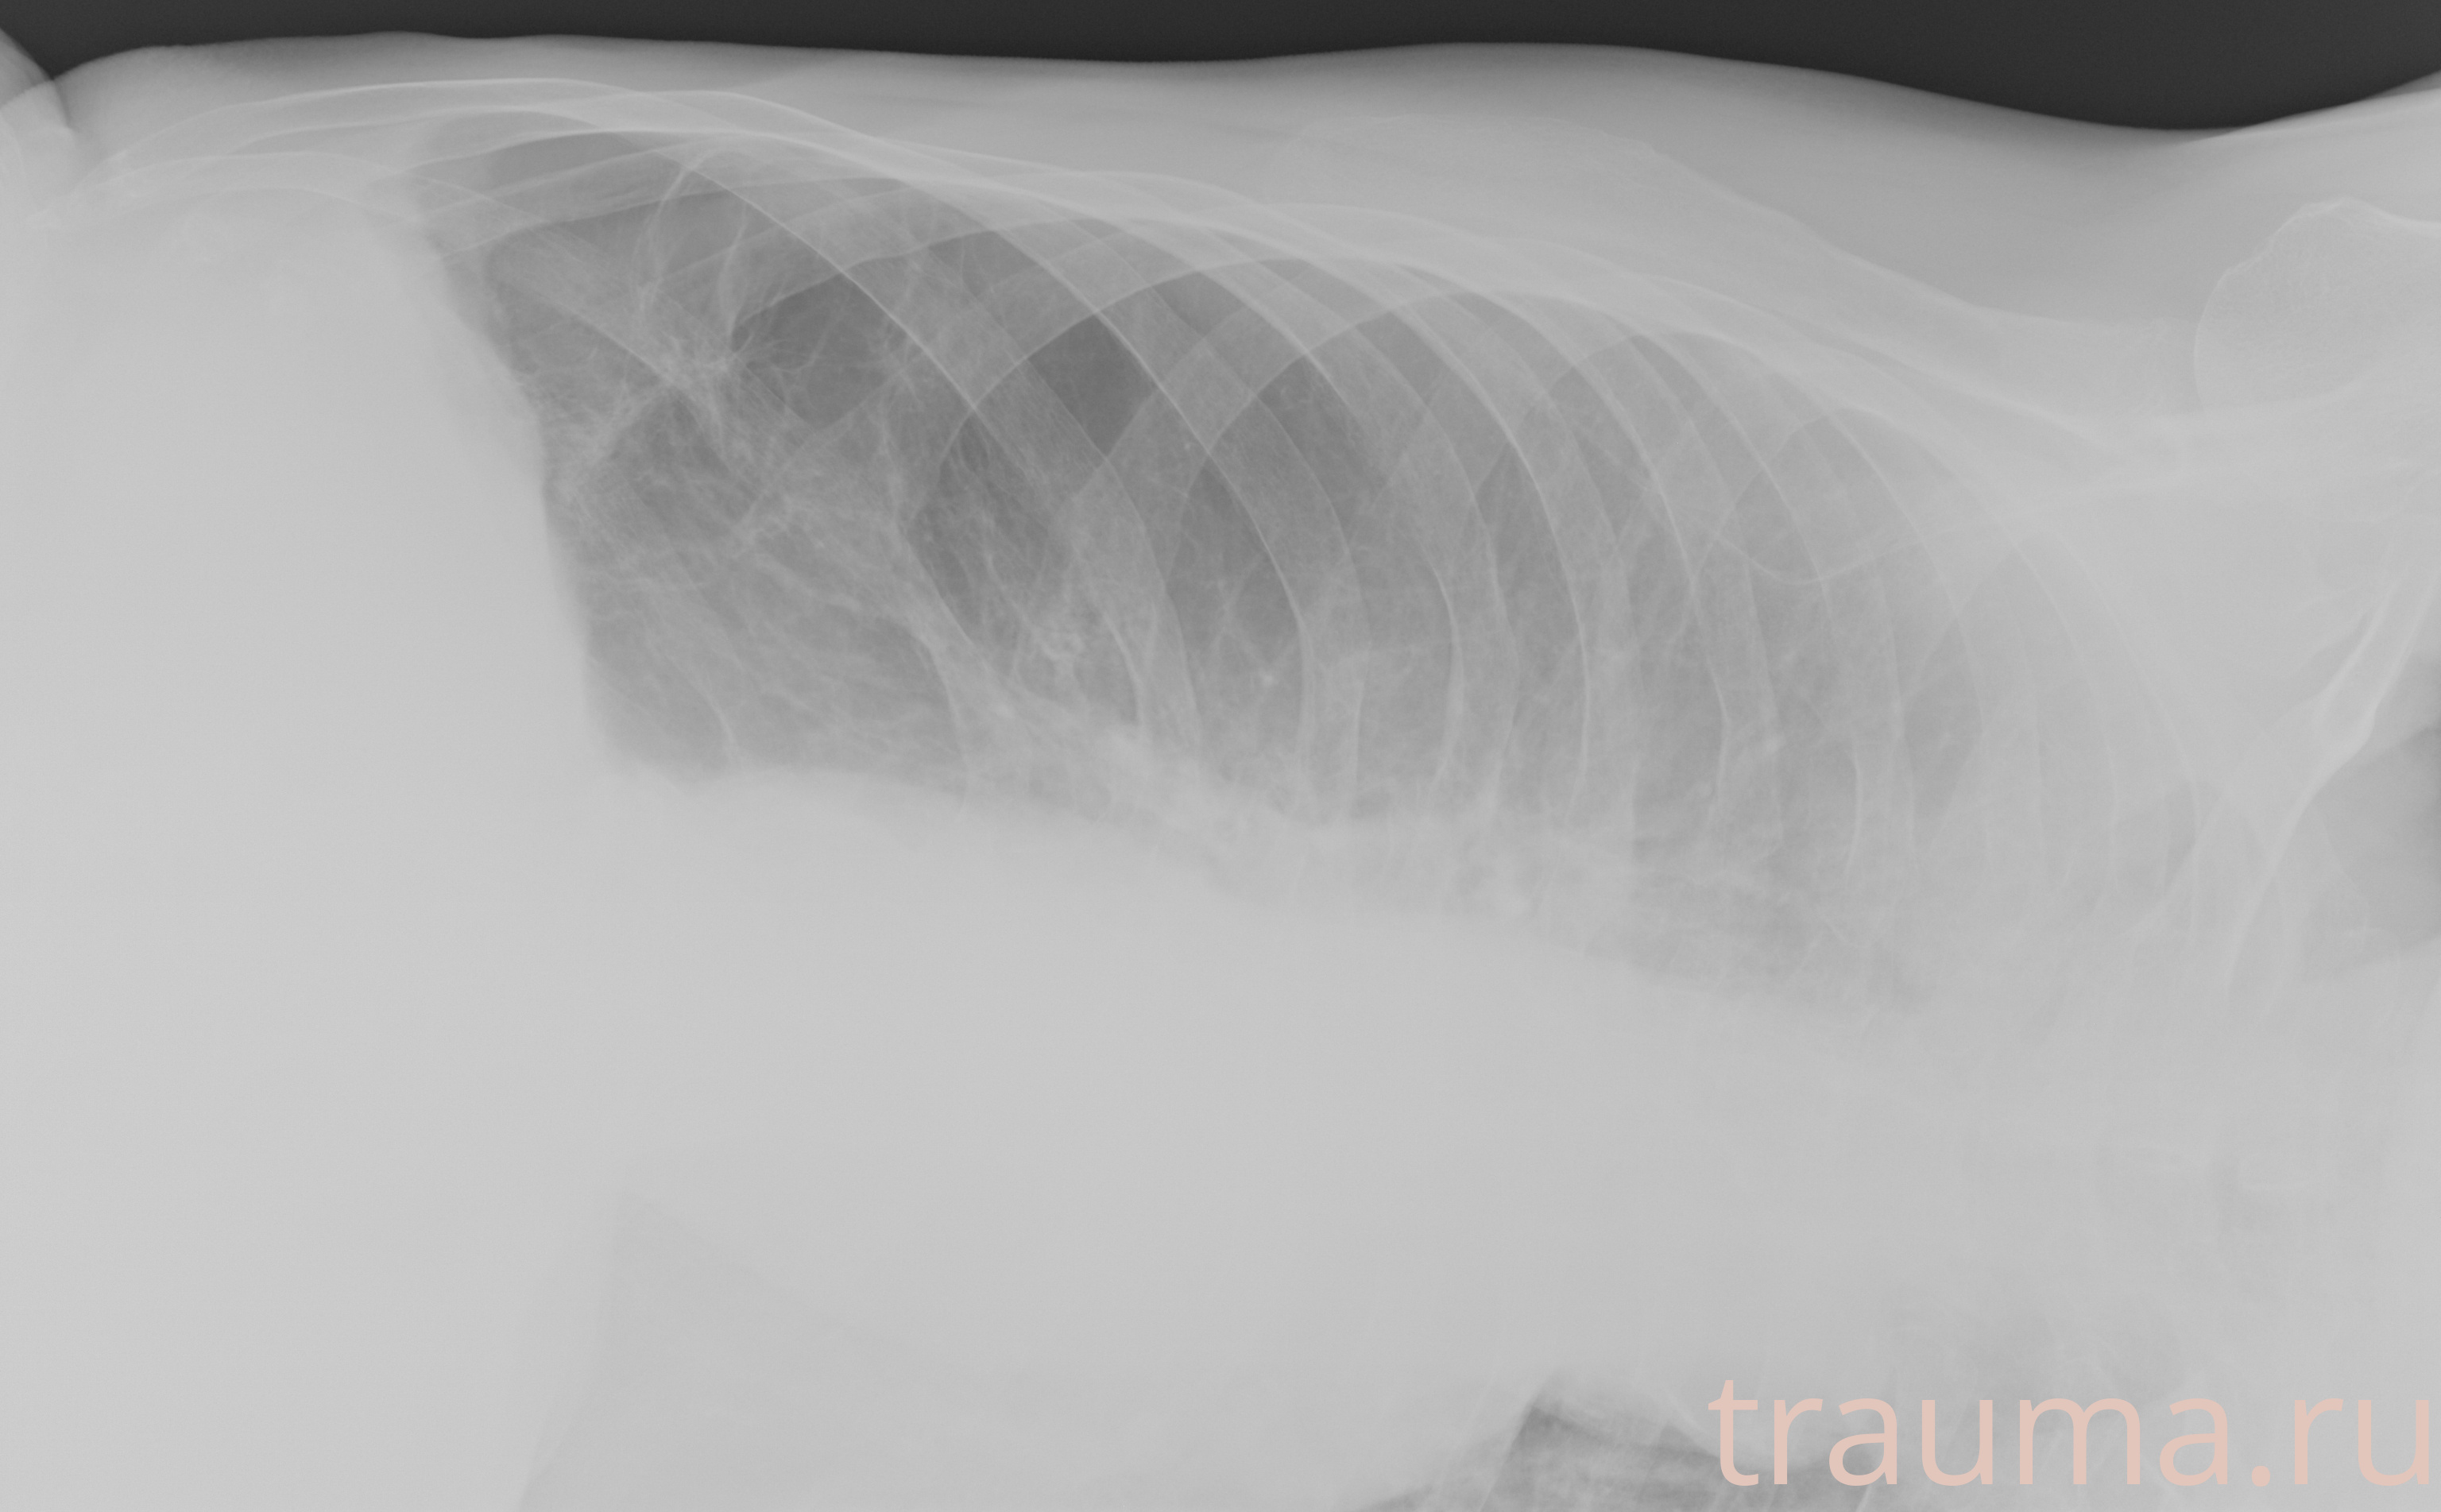

Рентген на дому: по вашему адресу приезжает врач-рентгенолог, травматолог-ортопед с мобильным рентгеновским аппаратом, проводит диагностику травмы или заболевания, делает необходимые рентгенограммы, дает рекомендации по дальнейшему лечению. Получить качественные снимки в домашних условиях возможно благодаря уникальной методике, разработанной МосРентген Центром для института  Склифосовского

при переломе шейки бедра и пневмонии от компании МосРентген Центр - партнера Института имени Склифосовского